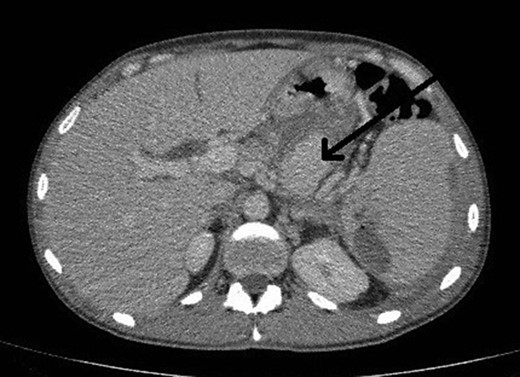

Selective angiogram using the Seldinger technique via left brachial approach to visualize the celiac trunk and superior mesenteric artery branches failed to show the pseudoaneurysm leading to the conclusion that possibly it had a different origin not accessible by angiography (Fig. 2).

Selective angiogram of the celiac trunk failing to demonstrate the pseudoaneurysm.